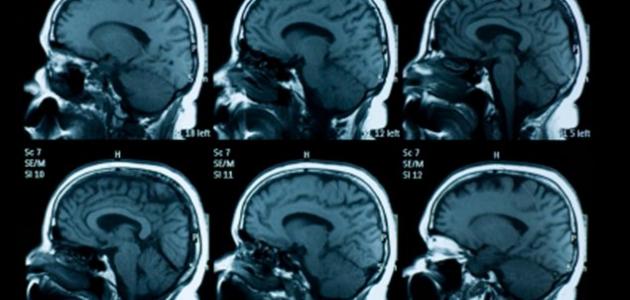

- فحص وتشخيص حالة المريض عن طريق زيارة الطّبيب، وعمل رنين مغناطيسي وتصوير طبقي للمخ.